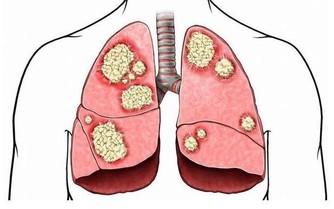

這種吃法曾被腎內科醫生稱為“最傷腎的吃法”。大量吃海鮮會產生過多的尿酸和尿素氮等代謝廢物,加重腎臟排泄負擔。而大量喝啤酒的話,腎臟發生疾病的機率會增高,也會讓尿酸堆積在腎小管裡面而出現堵塞情況,情況嚴重的人還容易造成腎臟衰竭。

很多人不愛喝白開水,反而喜歡喝汽水喝濃茶,但是這兩種飲品對腎臟的傷害都很大。如果有人每天喝兩瓶以上的汽水,出現腎臟疾病的機率會比正常人更高。據研究表明,如果長期喝汽水,腎臟功能會在二十年後會比年輕的時候衰退百分之三十。

而茶葉中含有咖啡因,少量飲用的話確實有提神醒腦的作用,但是經常飲用濃茶的話,含有咖啡因的濃度自然也會很高,就會給腎帶來巨大的負擔。